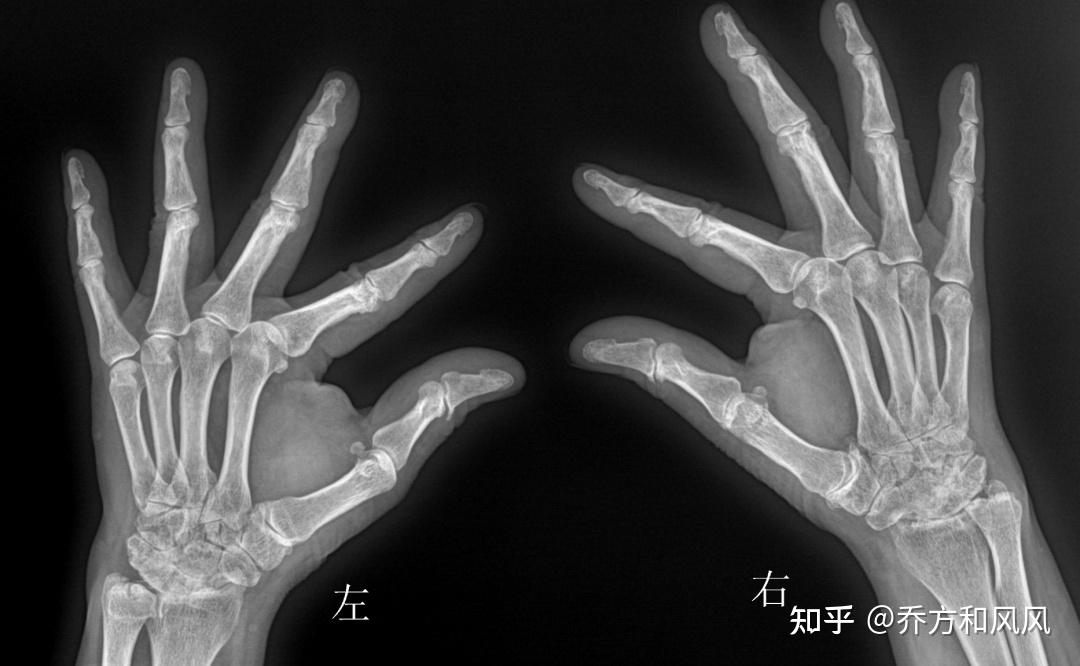

请各位老师看看,这是类风湿性关节炎引起的吗 - 影像医学和核医学讨论

图片尺寸3120x4160